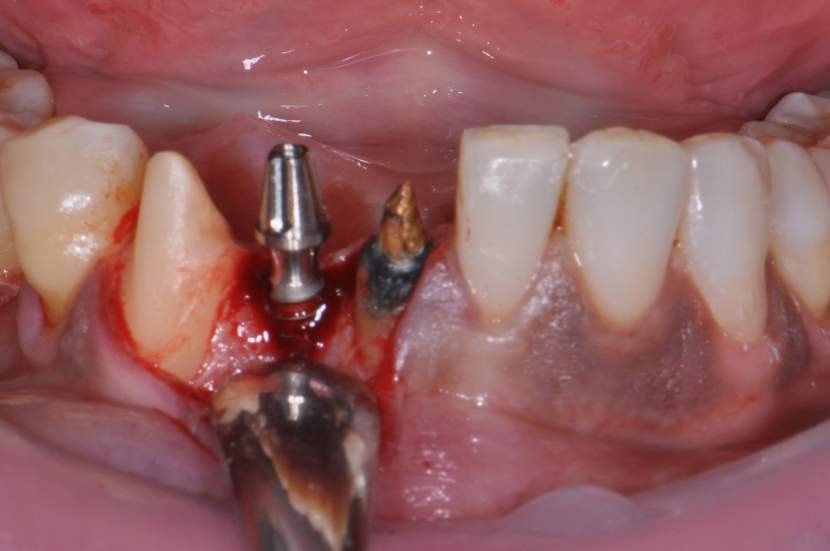

CASO CLÍNICO

Paciente com perda do incisivo central inferior do lado direito, utilizando uma prótese fixa em zircônia com estética e adaptação deficientes.